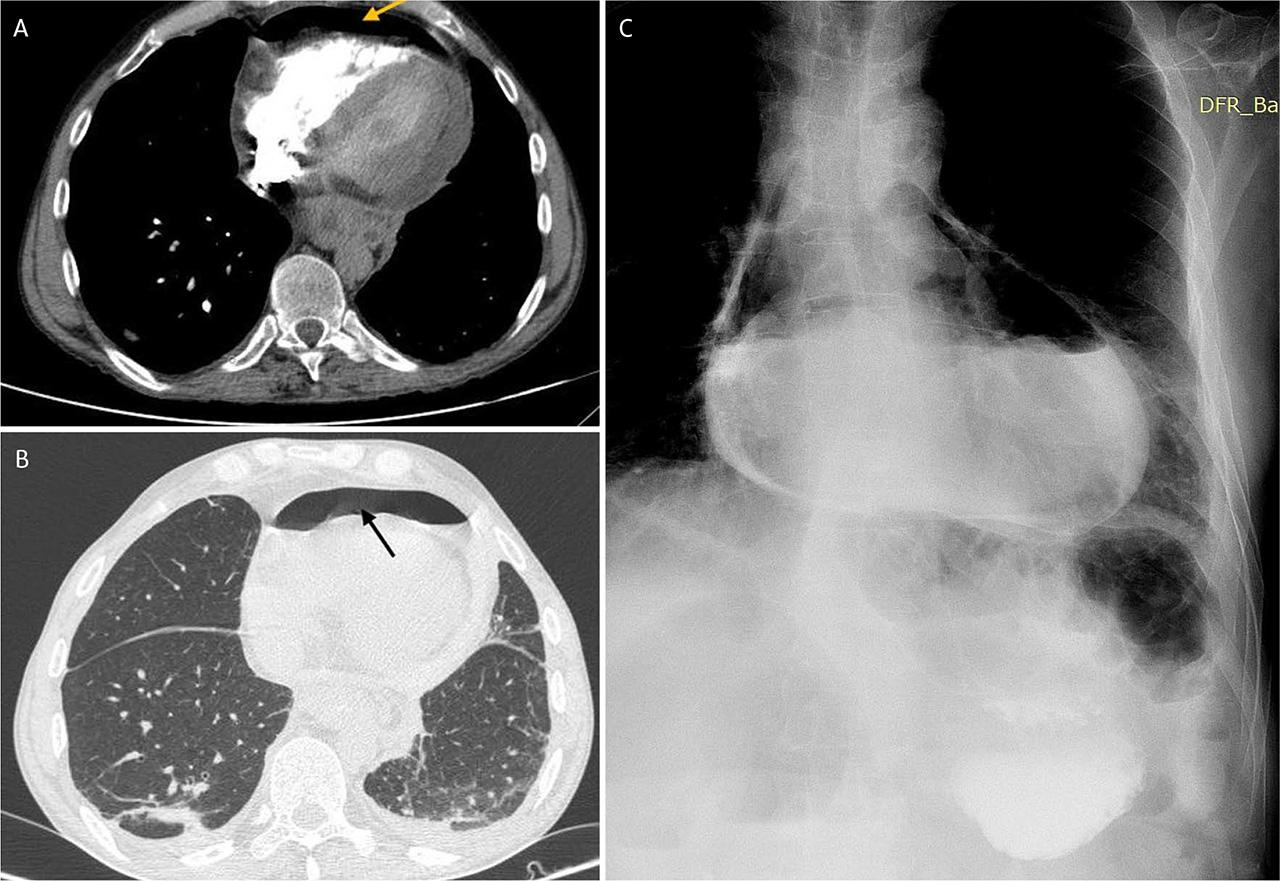

The patient underwent immediate coronary angiography. Obstructive coronary artery disease was excluded. However, a striking 20 mm hydroaeric image lining the inferior edge of the cardiac projection was visible (Figure 2). Following the angiography, an emergency chest CT scan was performed, which confirmed the hydropneumopericardium (the presence of air density of 13 mm and liquid of 18 mm in the pericardial cavity; Figure 3A), but also showed a circumferential thickening of the esophagus. Searching for a possible etiology, a Gastrografin study revealed a slight extravasation of contrast medium into the pericardial cavity, indicating a potential esophagopericardial fistula (Figure 3B). An emergency exploratory thoracotomy was performed to drain the purulent fluid from the pericardial cavity, but without revealing a fistulous path. After the procedure, the patient was transferred to the intensive care unit for monitoring and empiric antibiotic treatment.

A,B. CT scan, hydropneumopericardium. C. Extravasation of contrast in the pericardium during the Gastrografin study